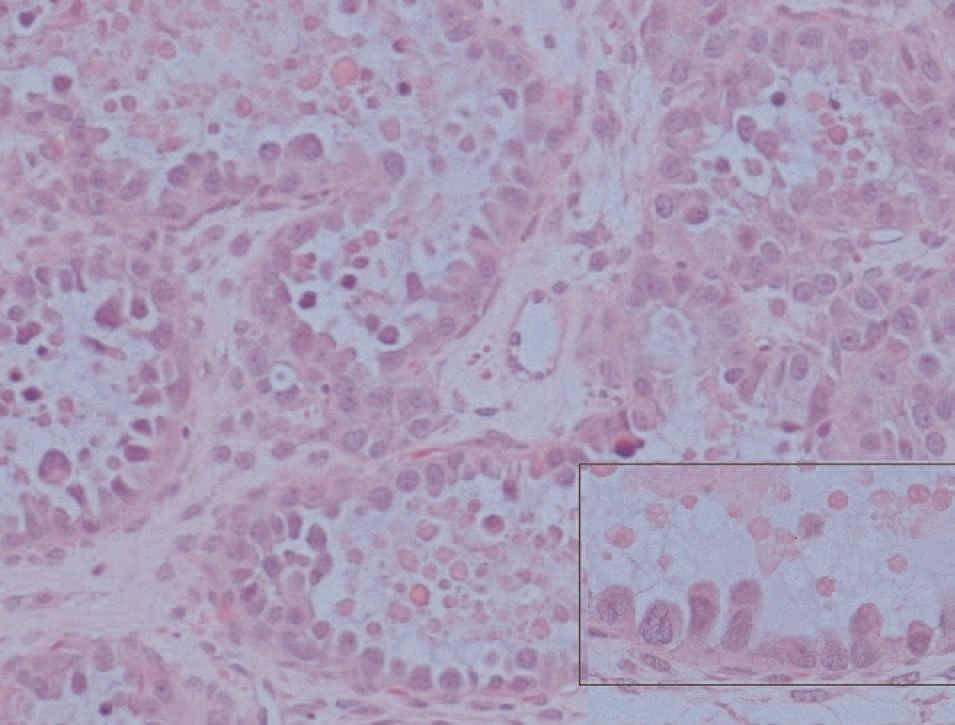

El estudio microscópico mostró, en la pared de la formación quística repleta de pelos, epitelio maduro de tipo escamoso queratinizado, con anejos cutáneos y fenómenos periféricos de reacción granulomatosa estromal a cuerpo extraño. No se identificaron otros tipos de tejidos maduros ni inmaduros, por lo que esta zona constituye un teratoma quístico maduro (fig. 3). El tejido carnoso que conformaba el resto de la tumoración presentaba histológicamente un crecimiento neoplásico de patrón tubuloquístico constituido por estructuras glandulares tapizadas por hileras de células cilíndricas o poligonales, intensamente atípicas, de citoplasma acidófilo, con frecuentes formas mitóticas que sólo ocasionalmente tenían citoplasma óptimamente vacío, y que adoptaban una típica disposición en «tachuela», característica de las neoplasias ováricas mesonefroides (fig. 4). En la luz de estas neoglándulas existían secreciones globulares eosinófilas PAS positivas. El estroma interglandular era escaso y sin atipias. No se observó endometriosis ni focos de carcinoma endometrioide. La cápsula tumoral estaba claramente infiltrada por esta neoplasia.

Figura 3. Microfotografía donde se observan tallos pilosos cortados perpendicularmente y rodeados de células gigantes multinucleadas de cuerpo extraño (A) y adenocarcinoma mesonefroide subyacente (B).Figura 4. Neoglándulas con epitelio monoseriado y secreción globular eosinófila. En el recuadro se observa con detalle la disposición «en tachuela» de las células neoplásicas con gran atipia citológica.